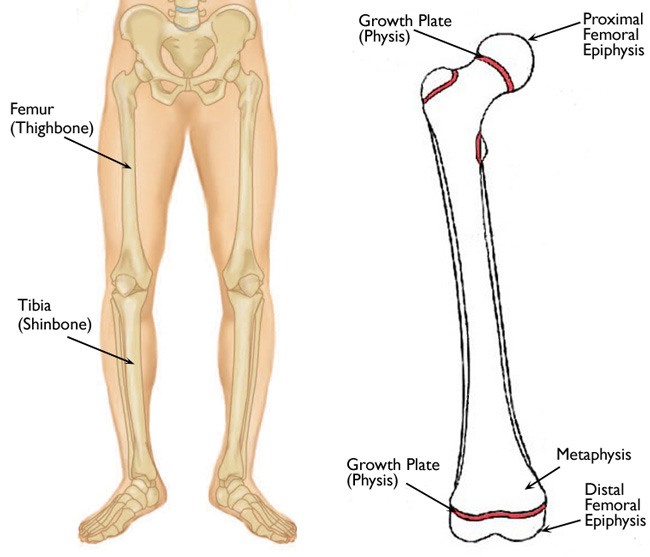

Физис это

Физис это 116 фото